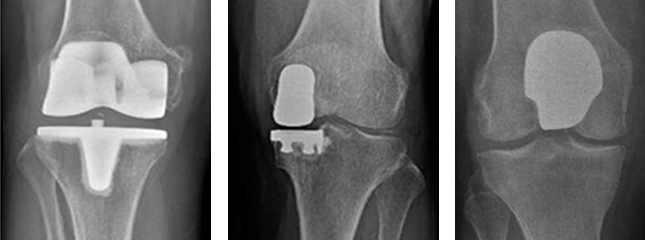

인공관절 보험물의 구성 인공관절 보험물의 구성 이미지

후방 안정 보형물 후방 안정 보형물 이미지

십자인대 보존형 십자인대 보존형 이미지

• 인공관절 보형물의 구성

인공관절 전치환술에 있어 세 개의 관절 면이 대체되게 됩니다.

• 대퇴원위부

금속 대퇴 보형물은 대퇴 원위부를 감싸는 형태로 되어 있습니다.

정상 원위부처럼 활차가 있어 슬개골이 움직일 수 있게 디자인되어 있습니다.

• 경골근위부

대부분의 경골 금속 보형물은 편평하게 되어 있는 것이 일반적인 디자인입니다. 그 위에 강하고, 질긴 플라스틱으로 만들어진 보충물이 얹혀지게 됩니다. 보형물의 안정적인 고정을 위해 경골 중앙부로 삽입되는 손잡이 부분이 있습니다.

• 슬개골 밑면부

슬개골 보형물은 돔모양의 폴리에틸렌이란 플라스틱으로 정상 슬개골과 유사하게 디자인 되어있습니다. 모든 금속 보형물은 플라스틱과 같이 움직이게 디자인 되어 있어 보다 매끄러운 움직임을 가능하게 합니다.

• 후방 안정 보형물

이 디자인에서는 경골 보형물의 쿠션인 플라스틱 모양이 대퇴 보형물에 맞아 들어가게 가운데 기둥이 있습니다. 후방십자인대는 제거 되어야 구성물이 뼈와 부착이 가능한 디자인입니다. 이 모든 구성물이 후방십자인대의 기능이 들어 있게 디자인 되어 있어서 대퇴골이 경골에 대해 너무 전방으로 빠지지 않게 되어 있습니다.

• 십자인대 보존형

이름 자체가 의미하듯이 후방십자인대를 제거를 하지 않는 디자인입니다. 이 디자인은 경골의 쿠션 가운데 기둥이 없으며 후방십자인대가 건강한 관절염 환자에게 시행되는 보형물입니다.